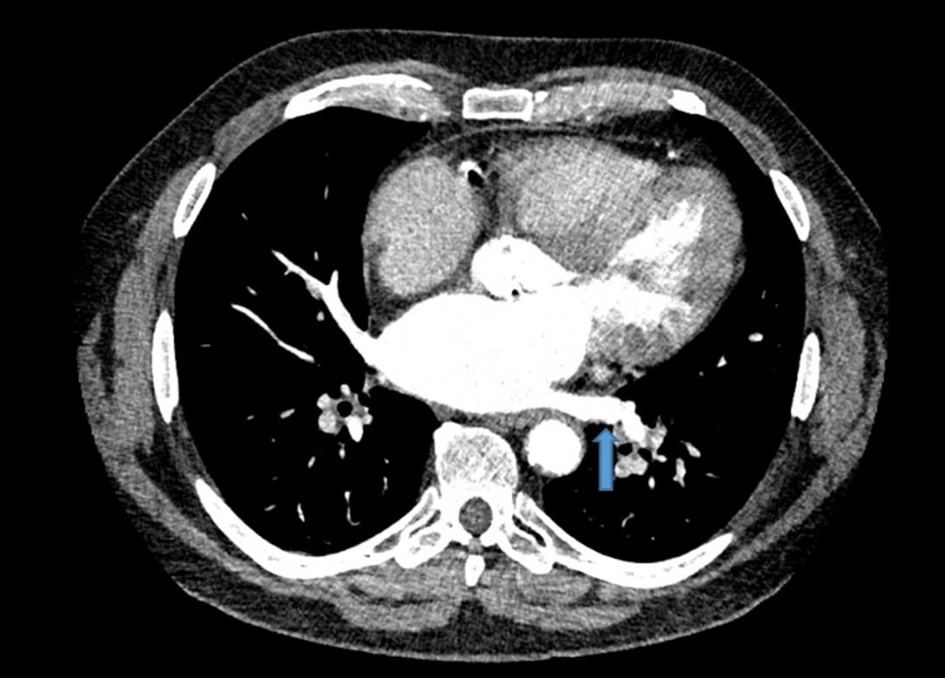

However, due to persistent neutropenia and rising liver enzymes, lenalidomide was lowered to 15 mg at cycle 5. This was further reduced to 10 mg by cycle 6 and 5 mg by cycle 10 for similar. During the 10th cycle, patient had a syncopal episode with worsening shortness of breath. Due to previously suboptimal stress test, coronary CTA was performed along with fractional flow reserve (FFR). CT-FFR showed diffuse atherosclerotic disease in left anterior descending (0.79) and left circumflex coronary artery (0.72) that did not warrant intervention. However, a thrombus in the left lower pulmonary vein was identified (Fig. 1). He was started on rivaroxaban 20 mg. Lenalidomide, dexamethasone and aspirin were discontinued. A 2-week follow-up transesophageal echocardiogram showed resolution of the pulmonary vein clot. Repeat CTA performed 2 months after initial diagnosis also confirmed clot resolution (Fig. 2). He had dramatic improvement in his dyspnea and remains off treatment for MM with plans to continue with rivaroxaban indefinitely given patient’s underlying malignancy.

![]() Click for large image | Figure 2. Resolution of left lower pulmonary vein thrombus. Repeat computed tomography angiogram revealed clot resolution after treatment with rivaroxaban. Similar transverse view of the chest is shown with blue arrow marking the previously seen thrombus location. |